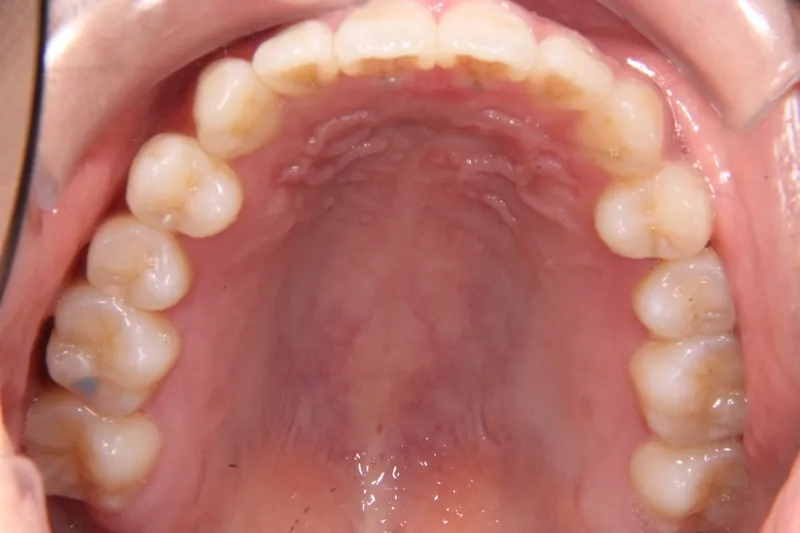

治療経過1

前歯で物が噛みちぎれないを主訴に来院された患者様です。

非抜歯で、オリジナルリンガルアーチと歯科矯正用アンカースクリューを用いて治療しました。

治療回数15回、1年の治療期間で矯正治療を終了しました。

主訴が改善され、ご満足頂きました。